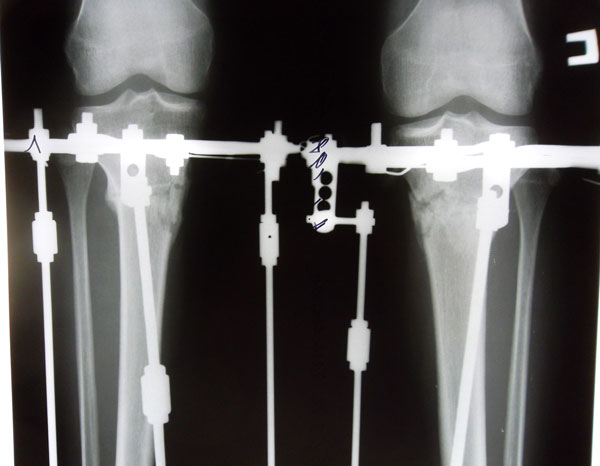

Рентгеновские снимки на момент снятия аппаратов.

Срок лечения 80 дней с момента операции.